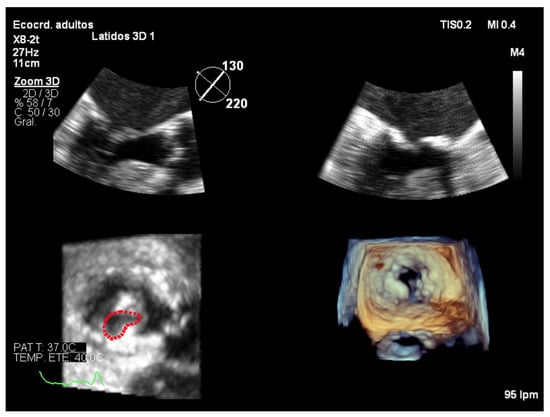

7.4. Focused Wide-Sector (3D Zoom) Imaging